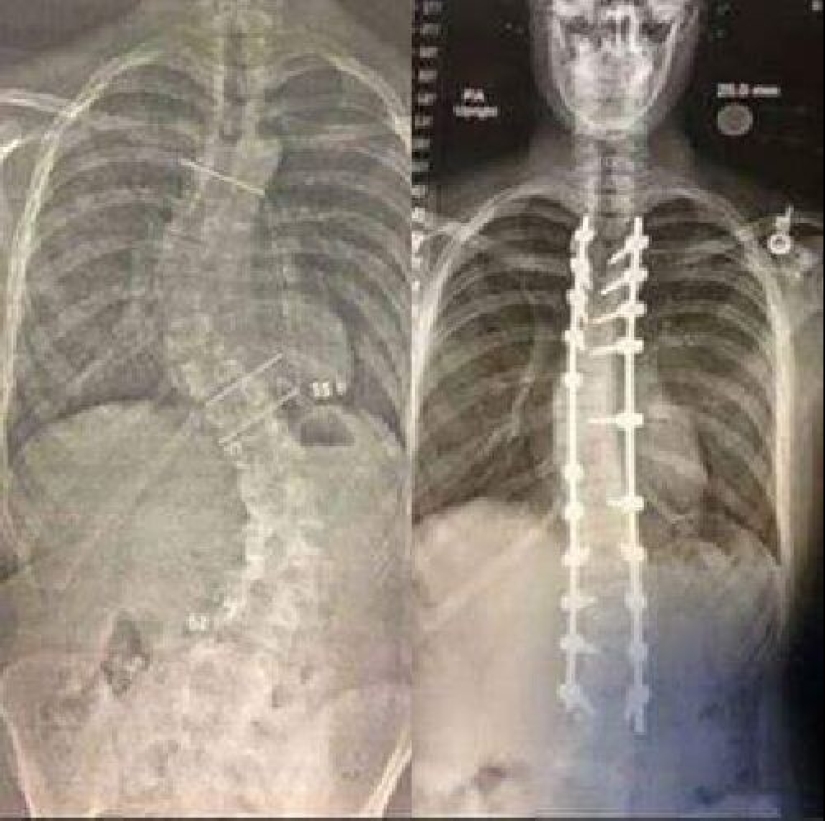

X-ray of the back before and after spinal alignment surgery due to scoliosis